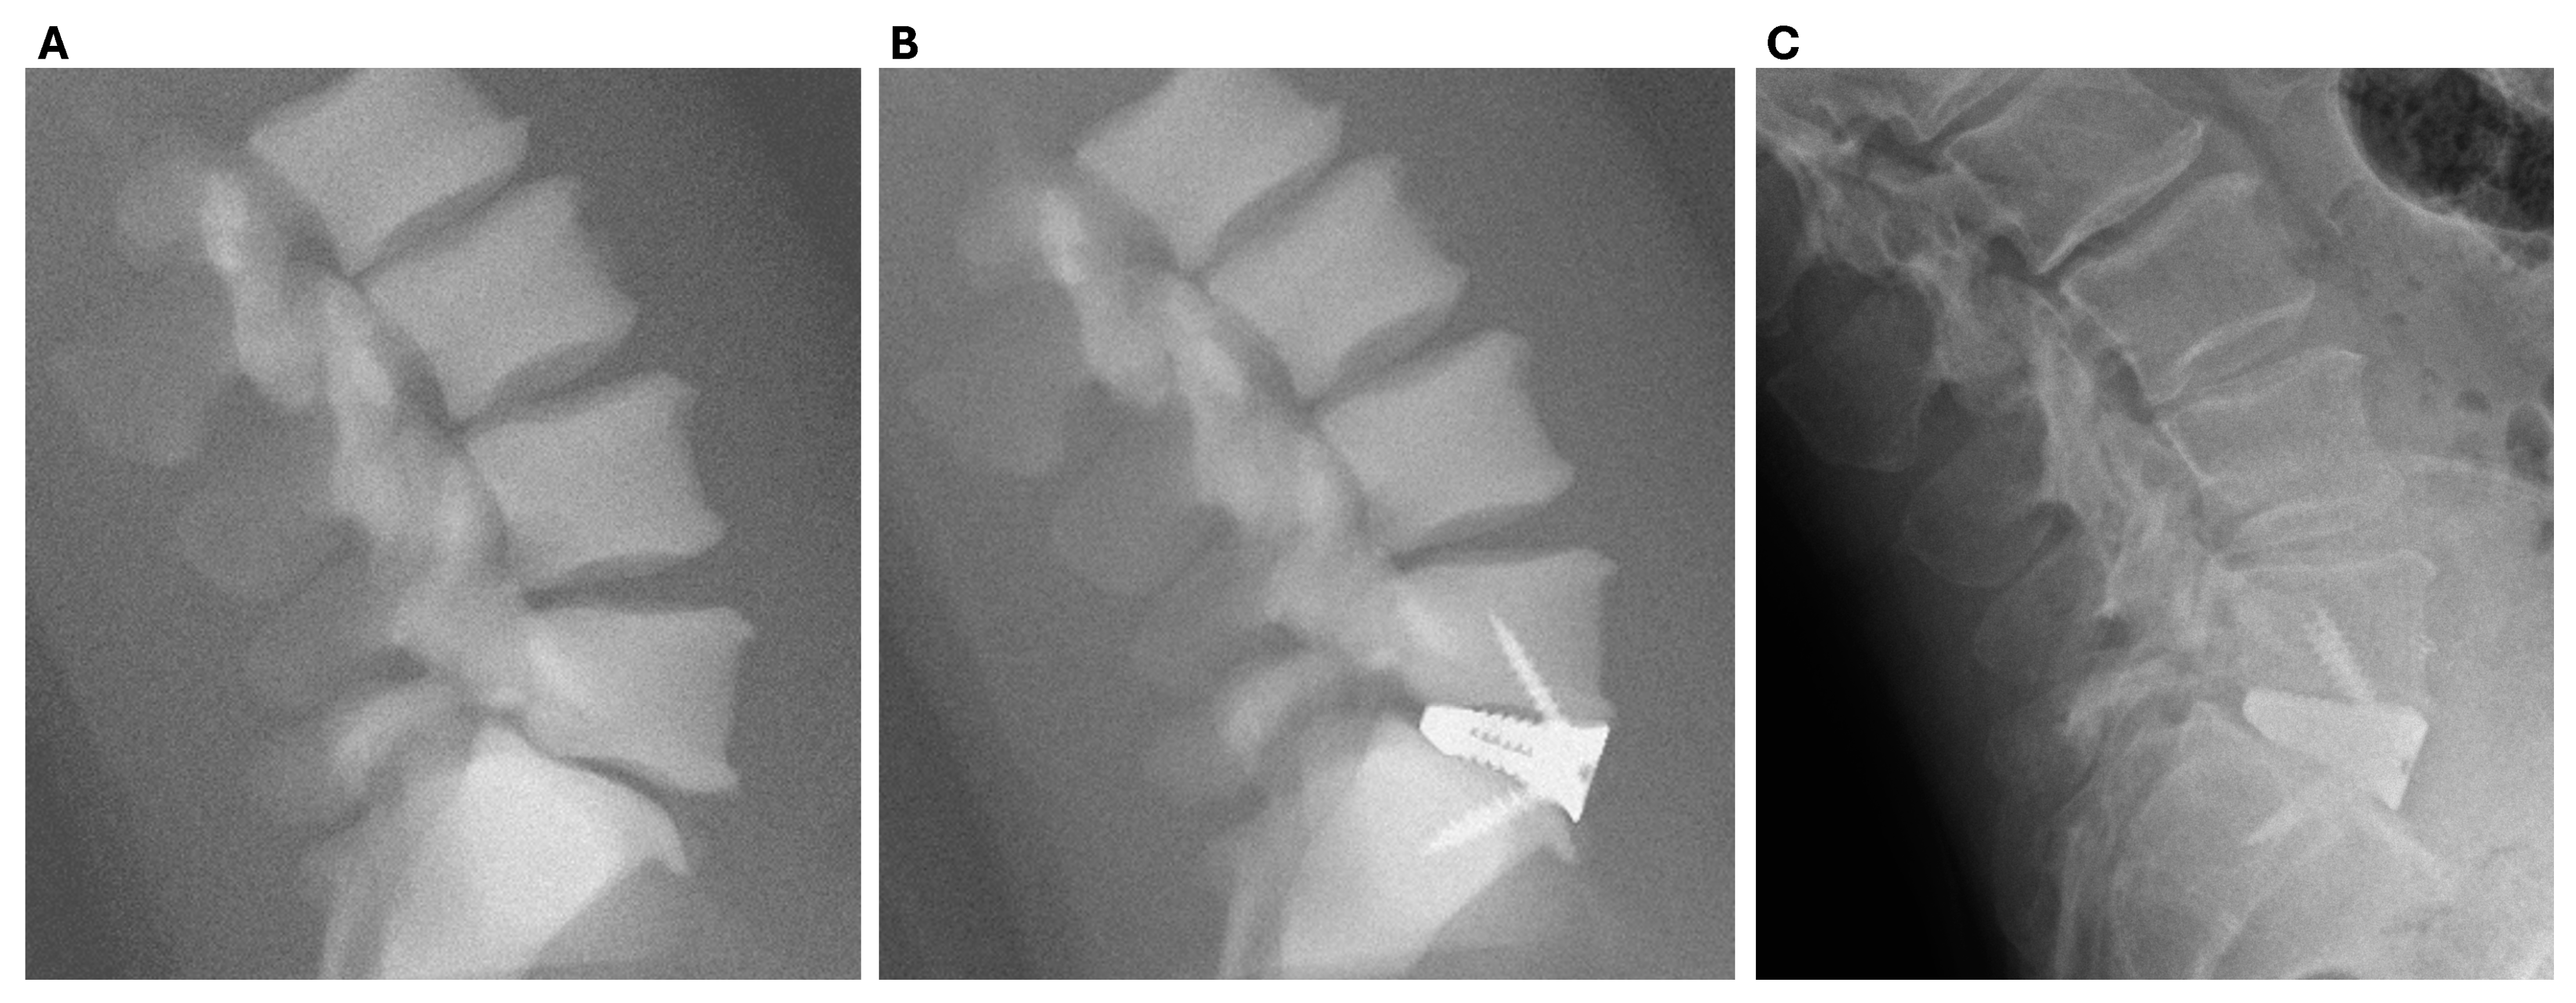

2.1.6. Operative Technique